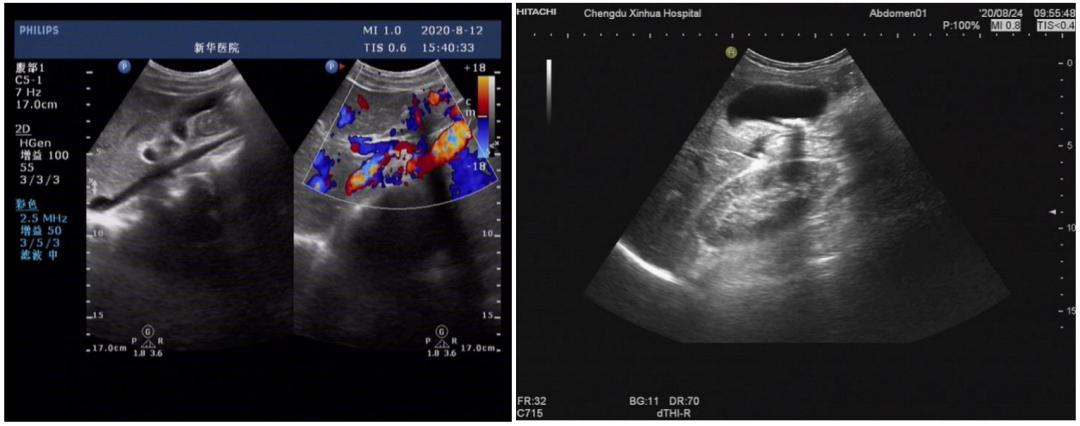

入院考虑肺部感染,予以抗感染治疗,同时常规行腹部彩超提示:胆囊壁胆固醇结晶。

治疗1周后患者突然出现上腹部钝痛,伴恶心。消化内科会诊后建议复查彩超后显示:胆囊大小形态正常,壁不厚,囊壁可见点状强回声伴声尾,囊内颈部可见长径约2.1cm强回声团伴声影,胰腺形态大小正常,实质回声均匀,胰管不扩张。

诊断胆囊结石,胆囊壁胆固醇结晶。后患者转入外科行胆囊切除手术。病例介绍2

两名患者,均是在入院后先后间隔1周左右复查腹部彩超或者MRI提示新发胆囊结石,是医技科室漏诊,还是其他因素所致短期内新发结石呢?

请彩超室高年资医生对比前后两次彩超图片,亦提示第一次检查未见确切结石影,第二次却见明显结石影,排除彩超误诊可能。

从患者用药入手考虑后发现两名患者均有长时间使用相同药物头孢曲松钠抗感染治疗,且使用剂量都为2g每天一次。查阅相关文献后,考虑头孢曲松钠所致的假性胆囊结石。